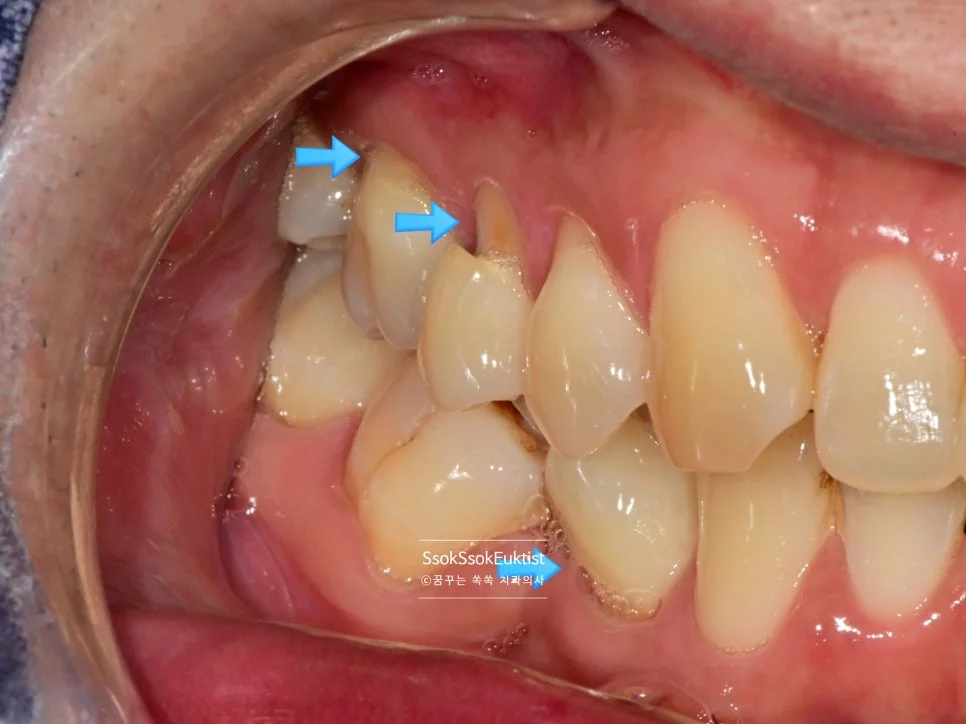

GI 치료 전 — 대부분 V자, 일부 U자 형태

형태를 보면 대부분 V자인데 하나 정도만 U자 형태를 보이고 있습니다. 이런 경우 강한 칫솔질이 치경부 마모증을 악화시켰다고 볼 수 있습니다!

이 사례에서는 GI(Glass Ionomer, 글라스 아이오노머)로 충전을 시행하였는데요.